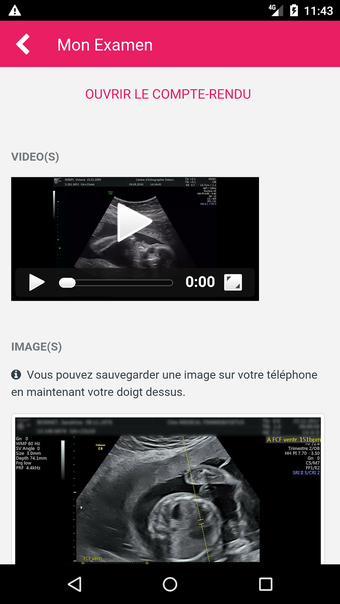

MediFile is an application for medical professionals to manage all of their ultrasound images, reports, and other patient data in one place. The application allows them to scan, view, and save their files directly from their device. The application has the capability to upload reports to the server of the doctor or midwife, for whom the report was sent.

The main advantage of the application is that it makes it very easy for the medical professional to view and share their patient's data with their colleagues. It also facilitates the creation of a patient database and a communication channel for all of the medical professionals working on the same case.